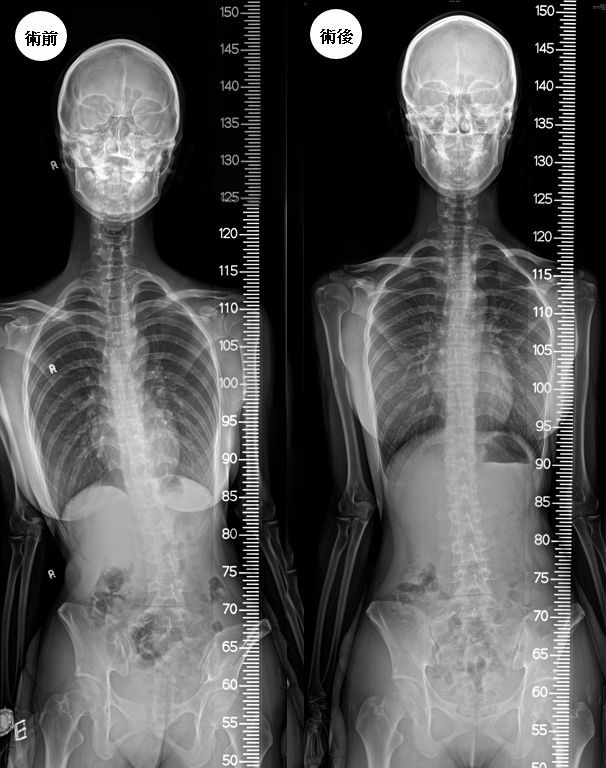

術前160公分高 術後167.5公分

術後蕭同學的疼痛指數減少至2分以下,側彎現象已明顯改善,身高從原本手術前160公分,術後恢復至167.5公分(圖3),還蕭同學一個亭亭玉立、揚眉吐氣的青春風采,蕭同學及家人相當滿意(圖4)。